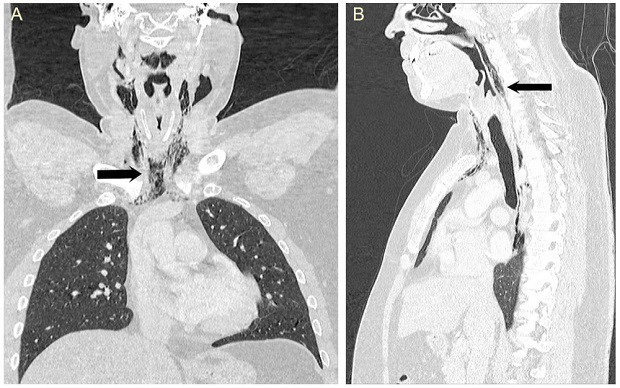

Пациенту сделали рентгенограмму, на которой врачи увидели чрезмерное скопление воздуха в мягких тканях шеи перед трахеей. Последующая компьютерная томография подтвердила образование большой эмфиземы в области шеи и грудной клетки. Тогда мужчине поставили диагноз «спонтанный разрыв пищевода».

Результаты компьютерной томографии шеи (B) и грудной клетки (A). На шее стрелкой указана эмфизема, в грудной клетке в районе позвонка T9 — эмфизема средостения

Wanding Yang, Raguwinder Sahota, Sudip Das, BMJ Case Reports, 2018